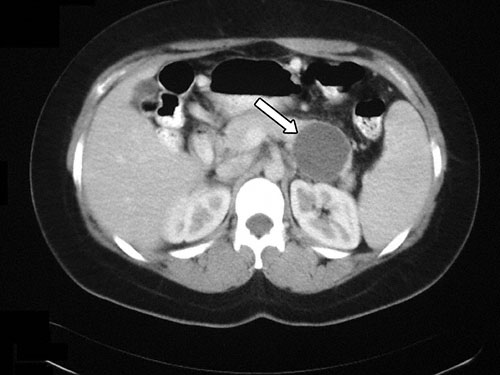

A 46-year-old woman comes to the office because of a 6-week history of upper abdominal discomfort and swelling. Six weeks ago, she underwent cholecystectomy because of severe gallstone pancreatitis that resolved slowly. She takes no medications. She is 168 cm (5 ft 6 in) tall and weighs 66 kg (146 lb); BMI is 24 kg/m2. Vital signs are within normal limits. Cardiopulmonary examination discloses no abnormalities. Abdominal examination shows a subtly palpable, 6-cm, mildly tender mass in the midepigastric region. CT scan of the abdomen is shown; the arrow indicates an abnormality. Which of the following is the most appropriate next step in management?